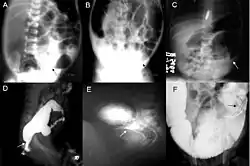

Definitive diagnosis is made by suction biopsy of the distally narrowed segment.[30] A histologic examination of the tissue would show a lack of ganglionic nerve cells. Diagnostic techniques involve anorectal manometry,[31] barium enema, and rectal biopsy. The suction rectal biopsy is considered the current international gold standard in the diagnosis of Hirschsprung's disease.[32]

Radiologic findings may also assist with diagnosis.[33] An abdominal x-ray can reveal a lack of stool in the large intestine or a bulging caused by blocked stool.[34] Cineanography (fluoroscopy of contrast medium passing anorectal region) assists in determining the level of the affected intestines.[35]